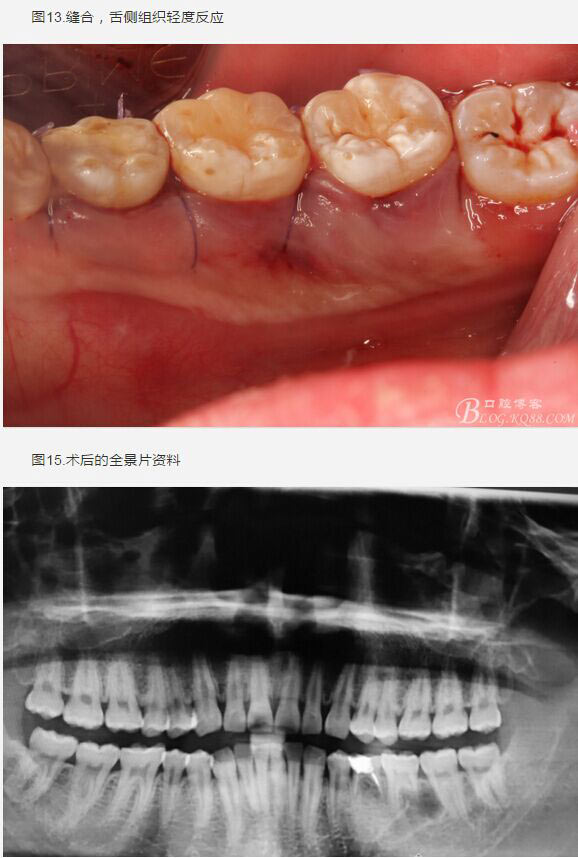

患者、盧xx、男、19歲。主訴:左側(cè)下頜乳磨牙未脫落,要求檢查。??茩z查:左側(cè)下頜第二乳磨牙有充填物。無松動,全景片檢查。35移位至36、37之間。頰舌側(cè)均不能觸及隆起。CBCT檢查:35位于36、37的舌側(cè)。表面骨質(zhì)約2mm左右。35完全骨埋伏,36的遠(yuǎn)中牙根疑是吸收。建議35暫觀察。置留不取?;颊咭蟀纬龘?dān)心壓迫36牙根或者發(fā)生囊性變。術(shù)前簽手術(shù)同意書。